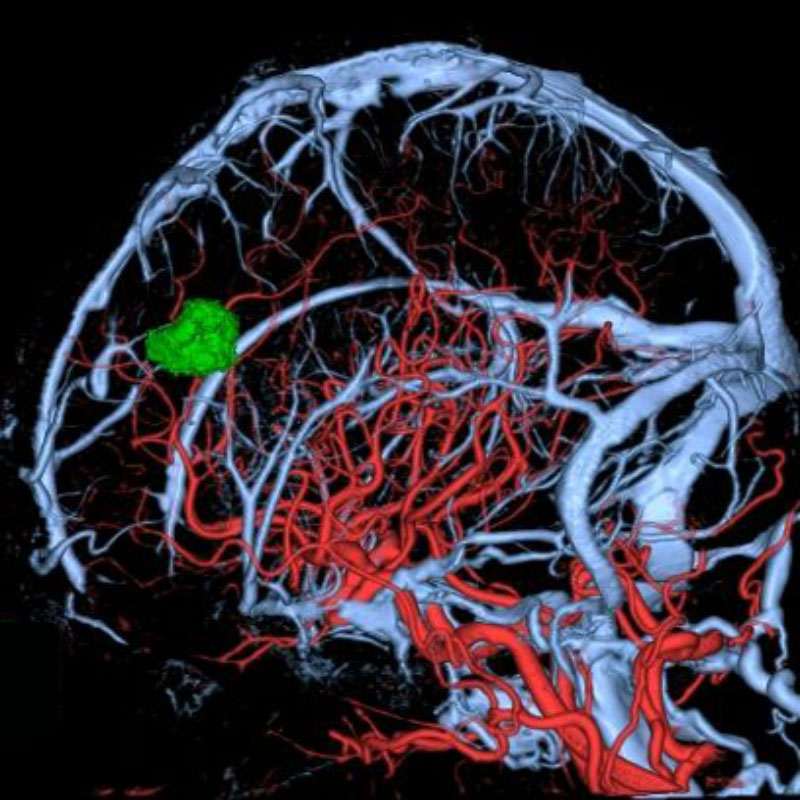

断層撮影

手術前1

手術前2